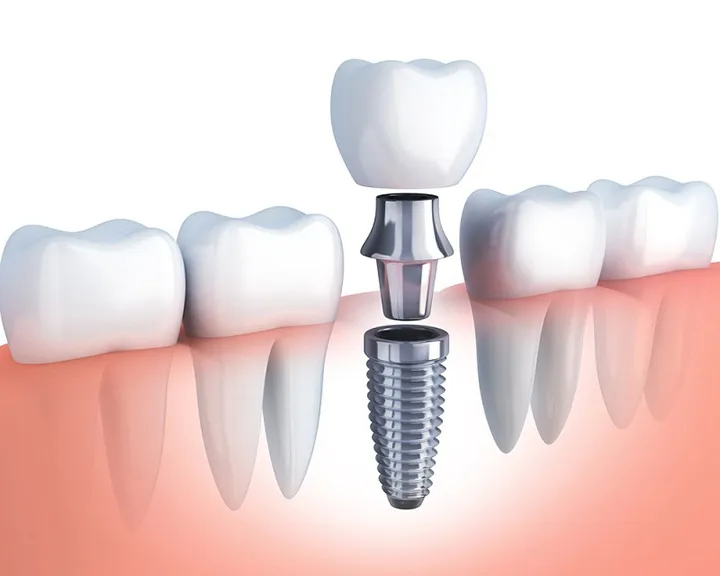

Vừa rồi chúng ta đã biết tủy răng là gì. Tuy nhiên, có một số trường hợp phải lấy tủy và bọc răng sứ. Lúc này, điều nhiều người quan tâm nhất đó chính là răng lấy tủy bọc sứ được bao lâu. Tuổi thọ của răng sứ sau khi phục hình có thể từ 3 – 20 năm phụ thuộc vào nhiều yếu tố. Trong đó chất liệu cấu tạo là yếu tố quan trọng hàng đầu. Mỗi loại răng sứ có độ bền, khả năng chịu lực và tính thẩm mỹ khác nhau. Thông qua đó ảnh hưởng trực tiếp đến thời gian sử dụng thực tế. Cụ thể:

- Răng sứ kim loại: Đây là dòng răng sứ có cấu tạo lõi bằng hợp kim kim loạ. Đồng thời được phủ một lớp sứ bên ngoài. Với chi phí thấp, răng sứ kim loại thường được sử dụng phổ biến. Tuy nhiên chúng có độ bền giới hạn, thời gian sử dụng trung bình khoảng 3–5 năm.

- Răng sứ Titan: Là sự cải tiến so với răng sứ kim loại thông thường. Răng sứ Titan có phần lõi hợp kim nhẹ hơn và ít gây dị ứng hơn. Răng sứ Titan có thể duy trì tốt chức năng ăn nhai và thẩm mỹ trong khoảng 5–10 năm. Đặc biệt khi được chăm sóc đúng cách và kiểm tra định kỳ.

- Răng toàn sứ: Đây là dòng răng sứ cao cấp nhất hiện nay. Nó được chế tạo hoàn toàn từ sứ nguyên khối, không chứa kim loại nên an toàn sinh học. Đồng thời không gây kích ứng nướu và có độ trong tự nhiên như răng thật. Tuổi thọ trung bình của răng toàn sứ có thể đạt từ 15 đến 20 năm. Thậm chí lâu hơn nếu được chăm sóc và bảo vệ tốt.

Chất liệu là yếu tố cốt lõi quyết định độ bền và tính thẩm mỹ của răng sứ. Trong đó:

- Răng toàn sứ (sứ nguyên khối) được đánh giá cao về độ cứng. Tại đây loại răng này khả năng chịu lực và màu sắc tự nhiên tương đồng với răng thật. Nhờ vậy, tuổi thọ của răng toàn sứ có thể kéo dài từ 15 đến 20 năm. Thậm chí lâu hơn nếu được chăm sóc tốt.

- Răng sứ kim loại, do có phần lõi bằng hợp kim nên dễ bị oxy hóa theo thời gian. Từ đó ảnh hưởng đến viền nướu và tính thẩm mỹ. Tuổi thọ trung bình của loại răng này thường chỉ từ 3 đến 5 năm.